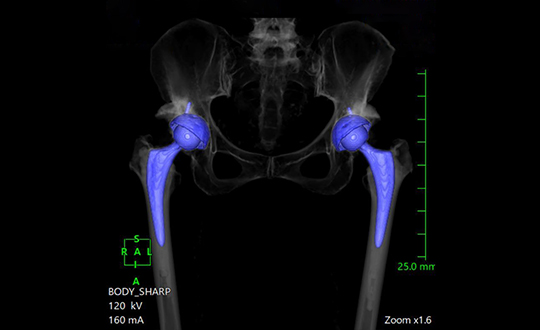

当病院では、人工関節置換術や骨切り術などの手術治療や再生医療にも対応しております。患者様をご紹介頂き、当病院で治療後に、逆紹介の形で患者様をお返しすることで、術後の検診や経過観察をよりスムーズに実施可能です。

高速・高精細撮影により短時間で体内を詳しく撮影できるCT装置。80列検出器による高速撮影とAIDR 3D Enhanced技術で被ばくを低減し、安全性と精度の高い検査を行います。

関節疾患、スポーツ障害、骨折など、幅広い症例に対応可能で、患者様一人ひとりに合わせた治療方針を提案しています。術前検査から術後フォローまで一貫した対応が可能であり、地域の先生方との連携のもと、必要な症例に対し迅速かつ的確に対応します。